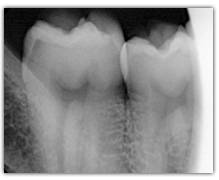

What represent the white, blue, red or black areas which can been seen on the tooth?

According to the pathologies of the tooth (destructured enamel, affected dentine, anfractuous fissure, presence of a crown…), the signal of fluorescence of the dentine will be different (weaker, darker, redder, absent…)

The light must cross the enamel to excite the dentine. Following this excitation, the dentine send back a signal of fluorescence which must cross the enamel to be interpreted. The thicker the enamel is, the weaker the signal of fluorescence is. The intensity of the green light will be weaker and gradually tinted with blue (because of the way through enamel). This is the case for the cusps